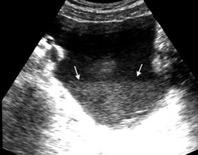

Patrón ecográfico de empiema

Anecoico.....0%. (0 de 47)

Complejo no septado no hiperecoico... ……………..0% (0 de 36)

Complejo, no septado hiperecoico......100% (2/2)

Complejo septado …35% (11 de 31)

Ecogénico homogéneo .... 100% (2 de 2)

Wang T et al. Value of ultrasonography in determining the nature of pleural effusion. Analysis of 582 cases. Medicine 2022.

Chih-Yen Tu et al. Chest Ultrasound Study Pleural Effusions in Febrile Medical ICU. Chest 2004